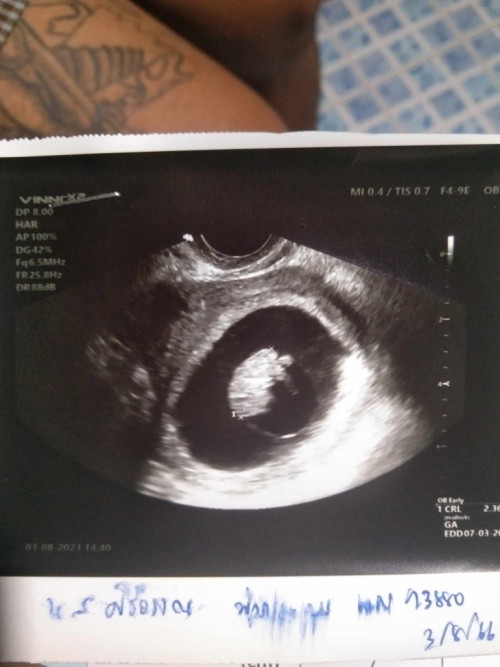

ตอน8+6วีคค่ะ ใจจริงอยากซาวด์ดูทุกวัน อยากเห็นทุกๆการเจริญเติบโตของเขา🥰

ตอนซาวด์น้อง 8 สัปดาห์จ้า ตอนนี้ 10 สัปดาห์พอดีเลย 🥰

ในรูป9 สัปดาห์ ตอนนี้11 สัปดาห์ 2 วันแล้วค่ะ